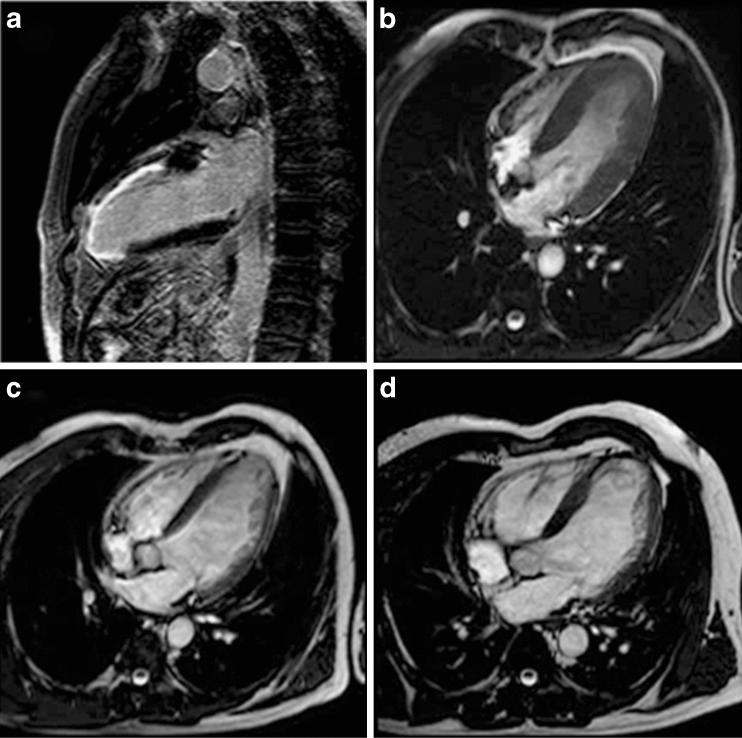

The emerging role of magnetic resonance imaging and multidetector computed tomography in the diagnosis of dilated cardiomyopathy.

Magnetic resonance imaging and multidetector computed tomography are new imaging methods that have much to offer clinicians caring for patients with dilated cardiomyopathy. In this article we briefly describe the clinical, pathophysiological and histological aspects of dilated cardiomyopathy. Then we discuss in detail the use of both imaging methods for measurement of chamber size, global and regional function, for myocardial tissue characterisation, including myocardial viability assessment, and determination of arrhythmogenic substrate, and their emerging role in cardiac resynchronisation therapy. ELECTRONIC SUPPLEMENTARY MATERIAL: The online version of this article (doi:10.1007/s13244-011-0101-8) contains supplementary material, which is available to authorized users.